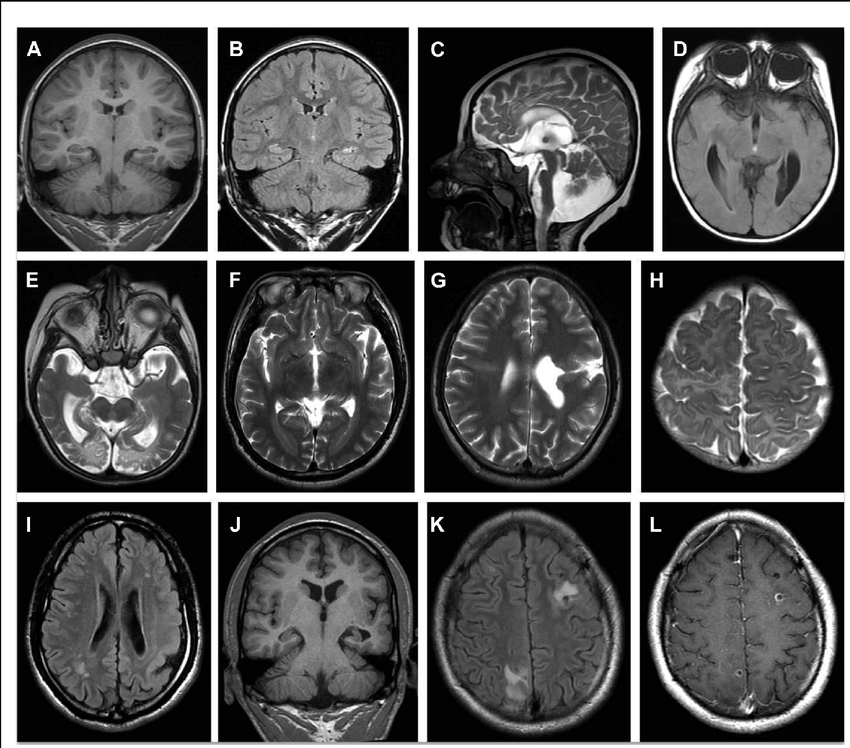

Od dodatnih dijagnostičkih metode kod epilepsije, najvažniji su: Magnetna rezonanca mozga i Elektroencefalografija (EEG).

Magnetna rezonanca mozga (MRI) treba uvek da se uradi prema definisanom protokolu za epilepsiju, što neurolog savetuje radiologu ili neuroradiologu, posle obavljenog neurološkog pregleda.

Postoje neke tipične promene na magnetnoj rezonanci mozga, koje su povezane sa određenim tipovima epilepsije.